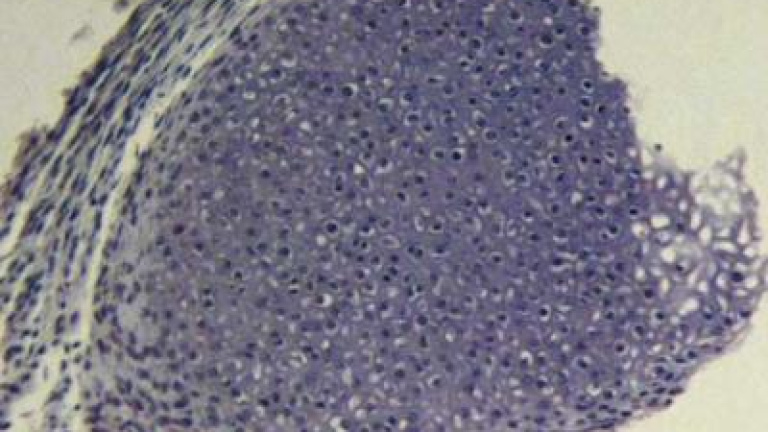

En esta carrera, el estudio de Daley logra recortar la lista a sólo dos, Oct4 y Sox2. Los demás promueven el crecimiento celular, pero son secundarios. Otro de los retos futuros en este campo de investigación es diseñar un método para introducir los genes que sea potencialmente compatible con el uso clínico.